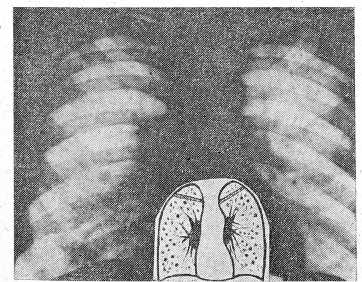

- Карциноматоз, имеющий сходство с диссеминированным туберкулезом легких, принято разделять на милиарный, мелкоочаговый й крупноочаговый. Все эти варианты объединяют общие черты: множественность очагов и близость рентгенологической характеристики с различными формами диссеминированного туберкулеза. Следует отметить, что такое деление в значительной степени условно, и у части больных, при динамическом наблюдении можно было констатировать переход мелких раковых узелков в более крупные. В рентгенологической картине очагов не удается обнаружить каких-либо черт, патогномоничных для диссеминированного рака. Можно лишь указать, что при крупноочаговой диссеминации в части случаев очаги отличались круглой формой, четкостью и ровностью контуров, что не свойственно диссеминированному туберкулезу (рис. 1, 2).

Рис. 1. Рентгенограмма легких больного Д

Рис. 2. Томограмма больного Д., 54 лет